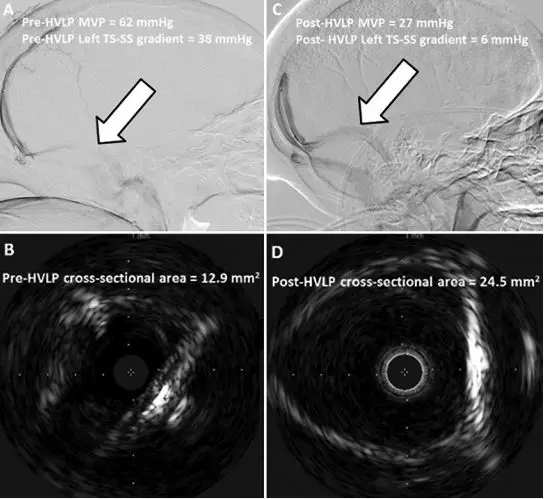

19.特发性颅内高压患者腰椎穿刺大量放液后静脉窦狭窄瞬时缓解

Transient resolution of venous sinus stenosis after high-volume lumbar puncture in a patient with idiopathic intracranial hypertension

PMID: 28841117 DOI: 10.3171/2017.3.JNS163181

横窦(transverse sinus,TS)和乙状窦(sigmoid sinus, SS)狭窄已运用于特发性颅内高压(idiopathic intracranial hypertension, IIH)患者的病理生理学研究。IIH患者行腰椎穿刺大量释放脑脊液(high-volume lumbar puncture, HVLP)后,MRI显示TS和SS狭窄改善,血管内超声成像(intravascular ultrasonography, IVUS)显示TS和SS的横截面积随之增加。TS-SS反复狭窄患者与HVLP颅内压开放压力升高相一致,静脉窦支架放置可以改善患者的临床预后。研究指出,TS和SS狭窄可能是IIH患者颅内压升高的下游效应,而不是其主要病因学机制。

【李信晓】